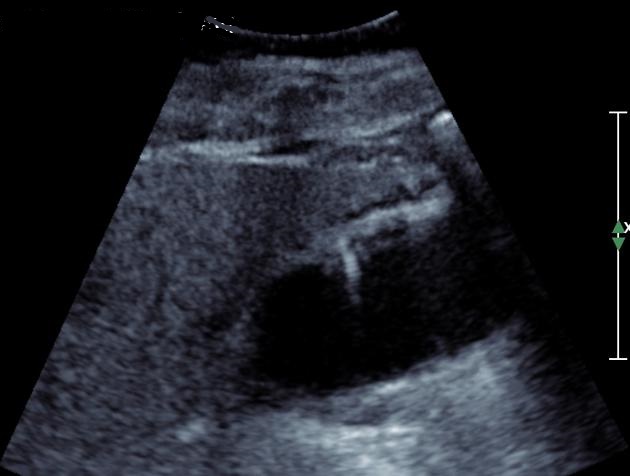

Image de

adenomateuse polyppoide isoechogenes de type sessile

: Image echographique en coupe longitudinale de la

vesicule biliaire |